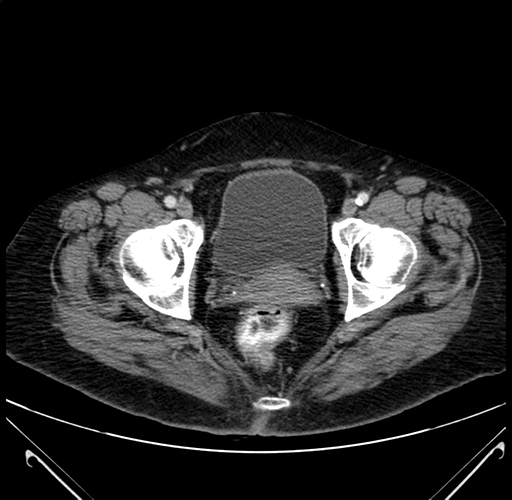

Pre-Chemo: Axial Venous

Axial Venous